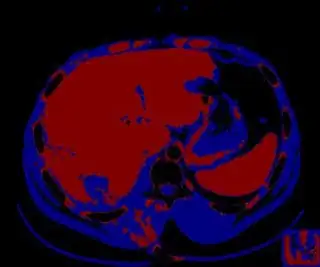

You might be able to narrow down the region or interest by filtering out the darkest and the lightest regions from the segmented image. For this, use the k-means cluster centers, check for the extreme values (max and min) and remove the corresponding k values from the labeled image. Then you can look for large structures to the left of the result image. Worst case, you might get a hole on the left side when the extreme region filtering goes wrong. I've updated the code and results.

Below are some of the opened and segmented images. Of course there's more to be done in terms of

- separating out the liver region

- generalizing this to a large dataset

but hope this is at least a starting point.